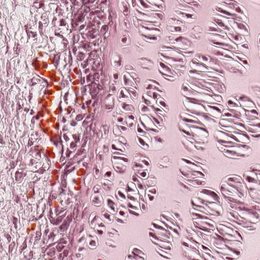

A cartilagem elástica possui uma composição semelhante à da cartilagem hialina. Entretanto, os condrócitos encontram-se isolados, e há uma abundância de fibras elásticas incorporadas à substância fundamental. Essas redes de fibras tipicamente são amareladas em um espécime fresco, enquanto em preparações histológicas elas podem ser facilmente visibilizadas usando colorações especiais.

A cartilagem elástica sempre é envolvida por um pericôndrio. Ela é encontrada no pavilhão auricular, no conduto auditivo interno, na tuba auditiva, na epiglote, na laringe e nos pequenos brônquios, onde sua flexibilidade e resistência à forças deformantes são funcionalmente importantes.